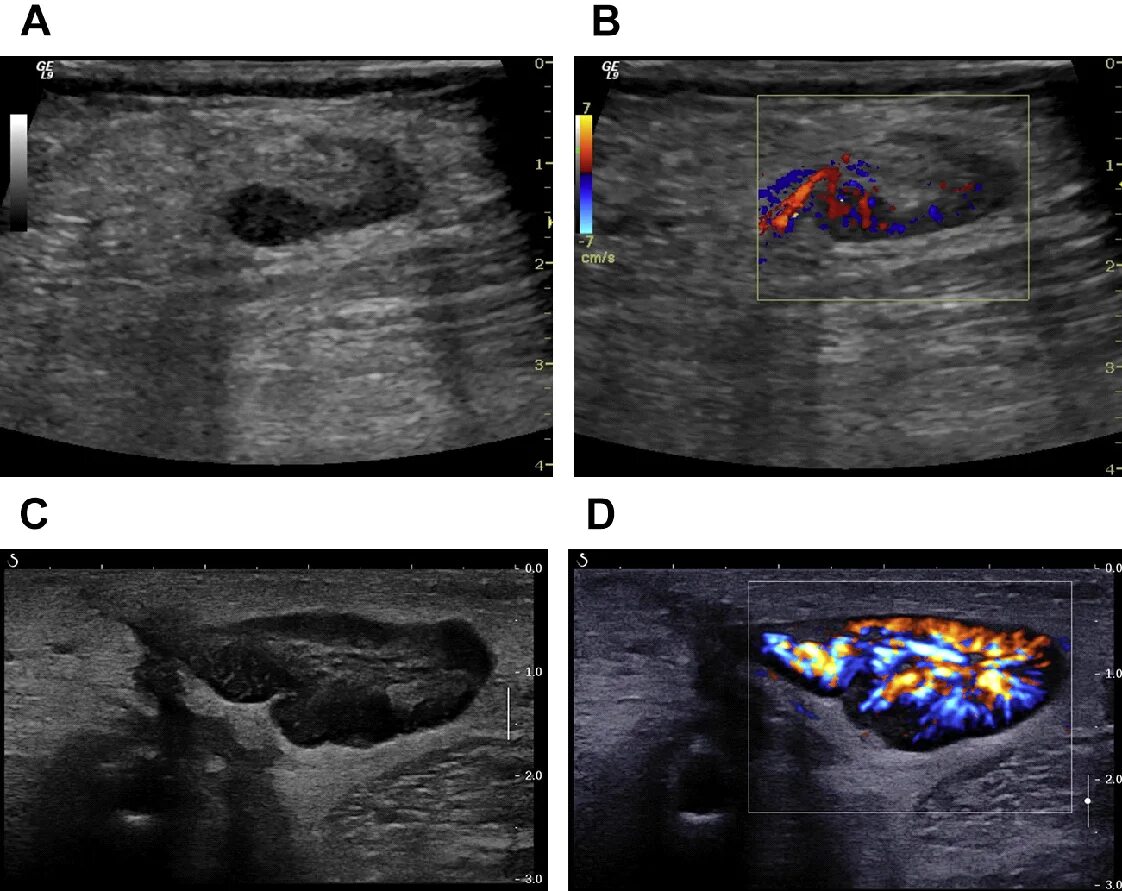

Метастазы в паховых лимфоузлах